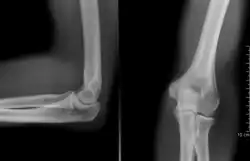

-

Codo humano izquierdo extendido -

Codo humano izquierdo flexionado